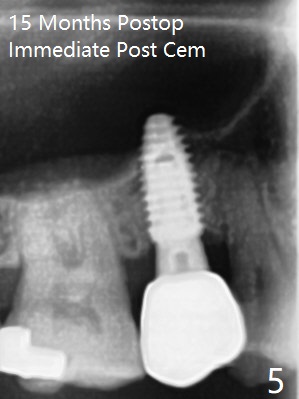

In fact the designed initial drills do not get to the bone with guides. After use of the next length drills (1.5 mm longer with sharp end), the sinus floor perforates without membrane perforation. Once 3.5 mm drill is used following sequential osteotomy, a 4x10 mm dummy implant is placed for sinus lift with 1 mm short of the depth and >50 Ncm. Following the dummy implant removal, allograft in the amount of 2 to 3 amalgam carriers is delivered for sinus lift (Fig.1,2 white *), followed by implant placement (4.5x10 mm, >55 Ncm). More allograft is placed before and after abutment insertion (black *). As usual, an immediate provisional is fabricated at each site. After removal and cleaning, the abutments are reseated and retorqued to 30 Ncm 11 months postop (Fig.3,4). Sinus lift is indistinct 15 months postop (Fig.5,6), probably due to radiation overexposure, although placement trajectory is good.